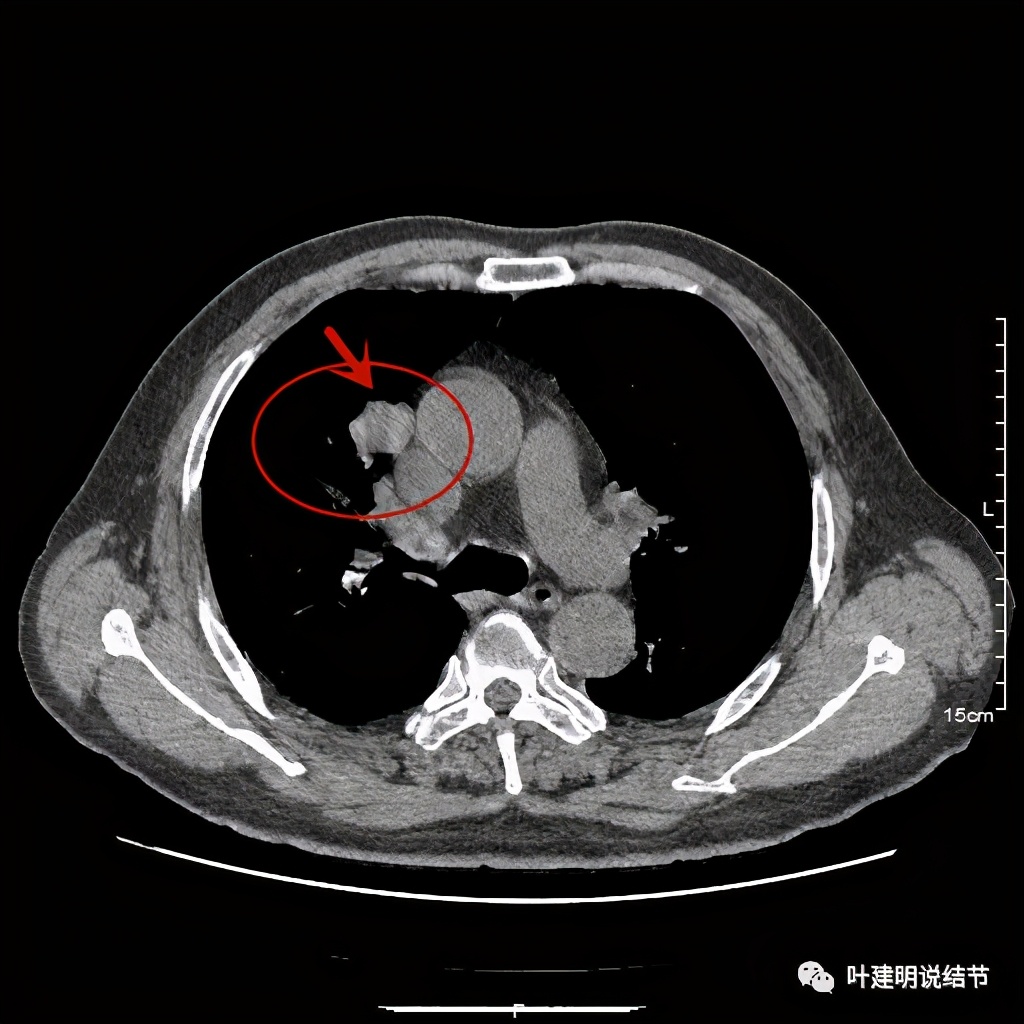

上图示病灶

上图示病灶密度不均